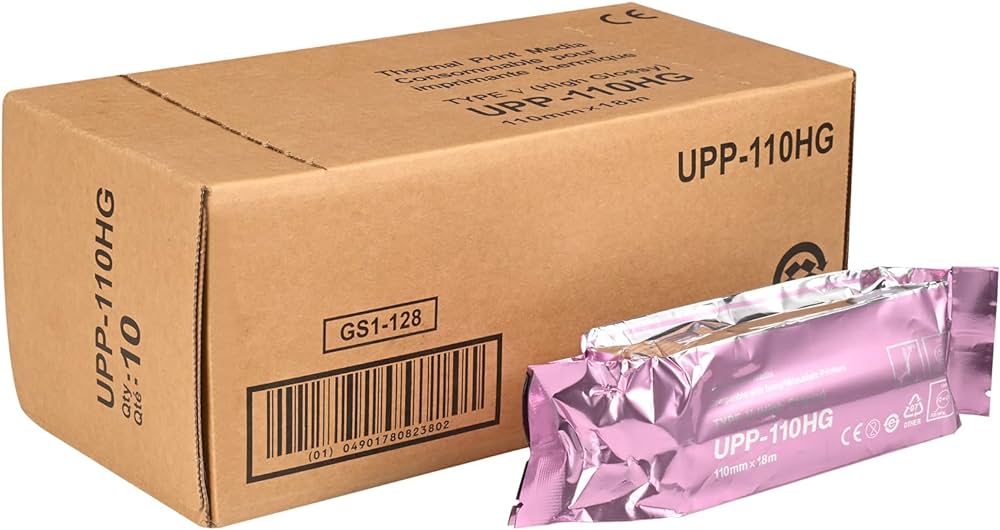

SONOMED Thermal Print Media SM 110 HG

Sony Ultrasound Paper Film/Media